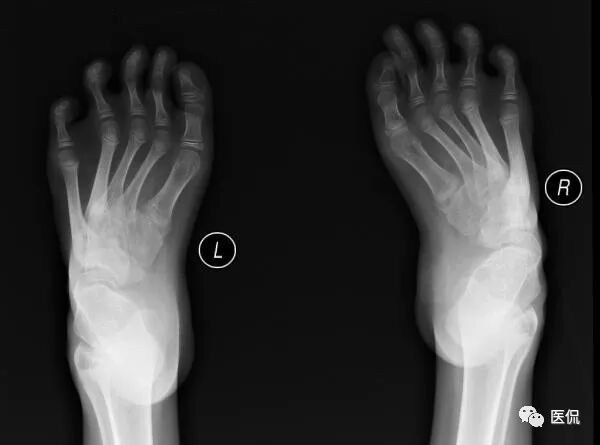

足部非负重正位片:足前部明显内收,跖骨远端及趾骨平铺,跖骨近端聚拢、外移;第1跖骨萎缩,第5跖骨肥大,密度增高;距骨扁而宽,距骨中轴线明显远离第1跖骨,跟骨内翻呈马蹄状,跟骨中轴线明显远离第5跖骨,跟距关节半脱位;跗骨形态失常,舟骨外侧发育较小,相应部分与距骨形成关节中创网,但距舟关节半脱位,跗骨关节间隙变窄;胫骨远端骨化中心外侧部分较内侧部分明显扁小。

因常规正位片踝部跟骨、距骨、跗骨及胫腓骨重叠较多,诸骨形态失常、变化较大,且测量误差增大,很小的位置改变即可改变足骨的关系,所以只要可能,正位、侧位片都应行负重位检查,但负重正位片受设备及投照的限制不易达到,因此角度的测量主要在负重侧位片上进行才更有价值。

解析:该患者临床上跟骨内翻、前足内收,不难理解,双足前部内收,跖骨近端聚拢、外移;足外侧着地,内侧悬空,第五跖骨近端刺激增多,造成肥大,第一跖骨刺激较少,引起萎缩,故A、B、D是正确的;C选项距骨向内移位足部骨骼图,很明显是错误的,因为跟骨内翻,为维持稳定,距骨会相应外移。

解析:该患者以足长轴呈内翻状态,足外侧着地,骨内弓减小,足外弓增大;距骨下部发育较小,邻近关节间隙变窄,致使距舟关节向上半脱位,舟骨位于跗骨的最高点;足内弓减小,足外弓增大情况下,必然引起跟距角明显减小;跟骨内翻,距骨相对外移,相应胫骨远端骨骺内侧部分刺激较多,骨化较大,故发育不对称足部骨骼图,腓骨骨骺亦会向后下方移位,故D选项错误。